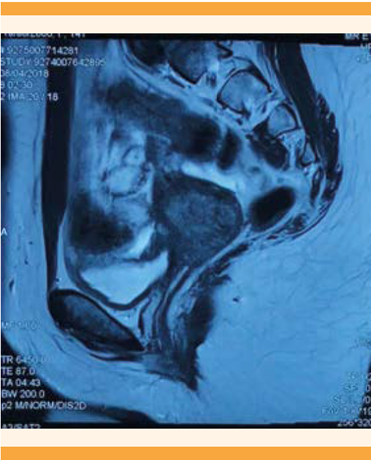

Posterior a la cirugía se dejó tratamiento con 9.25 mg de acetato de leuprolide. Dos meses después, la resonancia magnética de la pelvis reportó: útero en anteversión de 10 x 4 x 5.2 centímetros, con la cavidad endometrial ocupada por abundante contenido hemático y flujo retrógrado hacia ambas tubas. Esa cavidad, hacia la porción distal, terminaba en un fondo de saco cerrado (Figura 2). Durante el estudio, la cavidad vaginal se llenó con gel para distender las paredes. El tercio medio y distal se advirtieron normales en amplitud y grosor. No se formó el tercio superior y solo se identificó tejido fibroso interpuesto con una separación aproximada de dos centímetros (Figura 3) y se observó aplasia en el tercio superior de vagina.

Figura 2 Corte sagital de la resonancia magnética con la hematometra y la aplasia en el tercio superior de la vagina.

Figura 3 Corte sagital de la resonancia magnética. Se aprecian la cavidad vaginal con el gel y la aplasia del tercio superior de la vagina.